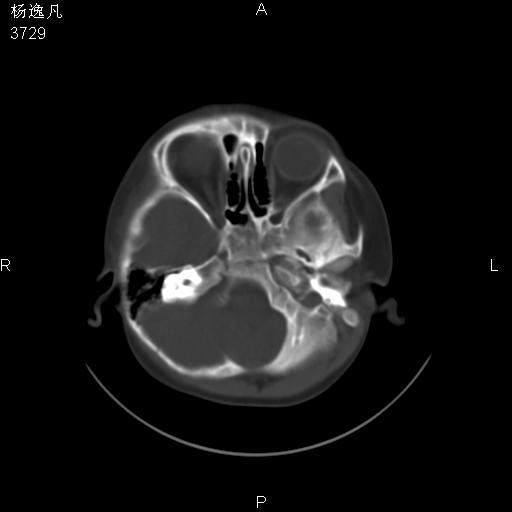

男性,5岁,面部受外伤,余无特殊

薄层

鼻咽顶后变窄。顶后壁增厚,考虑腺样体肥大。其它未异常/

头颅ct平扫未见明确外伤性征象,右侧面部及颞部软组织肿胀,后鼻腔软组织影增大,增厚,鼻咽顶部变窄,考虑鼻咽腺样体增值肥厚。